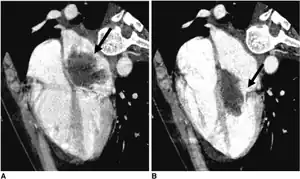

| CT left atrial myxoma | |